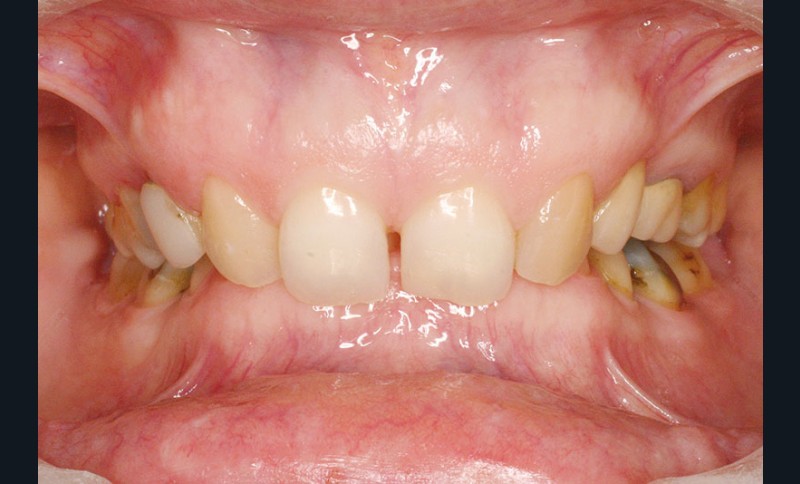

Malocclusion de classe II par rétrognathie mandibulaire dans un schéma squelettique hypodivergent (fig. 4 à 6).

On note une forte supraclusion incisive (fig. 7 à 9).

Un traitement orthodontique a déjà été effectué pendant son adolescence avec un choix de fermeture d’espaces qui a entraîné une linguoversion incisive maxillaire excessive (fig. 10), avec un préjudice esthétique important notamment sur le sourire (fig. 11 à 13).